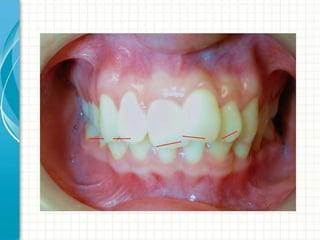

TORQUE?

Torque control

• You need a

rectangular wire

in a bracket.

Torque: only with rectangular wires

Torque

Torque correcion and arch form

development

6 to 7 appointments

NitiWiresize

0.014

0.016x0,025

Sequence ( normal for the MGH)

0.016